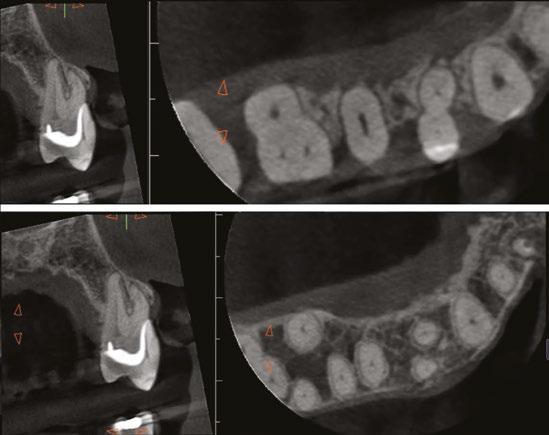

Judy McIntyre, DMD, MS Figure 1: Acutely curved and calcified buccal canal right under upper left premolar crown margin; valuable information for access and management. No. 9 also has a PARL, which was only incidentally captured Figure 2: Large PARL with destruction of the maxillary sinus floor and sinusitis as a result

About 10 years after completing residency, I opened my own practice and invested in a DEXIS CBCT. Initially, I only used it for apicoectomies and retreatments. In time, I began to realize how helpful it was for all my cases. With the 3D-scan information (Figure 1), I could have saved myself some humbling experiences and surprises. Endodontists hate surprises, and we really hate failures! Once I started using my CBCT more frequently, I was able to appreciate things that would have otherwise been intra-op surprises and plan for them prior to starting the procedure. The 3D data allows me to properly assess prognosis, determine the best course of treatment, and plan that treatment with a level of precision that is impossible otherwise.

CBCT also allows me to capture issues I might have previously missed, whether related or solely incidental findings. Practitioners can visualize pathology/issues even when a patient is completely asymptomatic. I had a patient referred to me with an issue on one tooth. Cone beam revealed the patient had four teeth that unfortunately needed extractions, and all previous imaging gave no indication of this. Another patient presented for one tooth, but the CBCT showed several cracked molars and a perforated post. I was able to properly diagnose those problems as well. Sadly, those couldn’t be saved with endodontics, but knowing that up front saved time, unnecessary treatment, and resources for the patient.

On a recent second molar case where I did not take a 3D scan prior to root canal treatment, the patient returned several days later still in pain! I took a scan and appreciated their deep split, forked in the last 5 mms of the distal canal (Figure 8). Without a CBCT scan, it’s easy to miss — I did! CBCT helps prevent this from happening by catching those variants and hard-to-find issues, which are not as rare as we think. This was another case that helped shape my current imaging protocol, so that now I scan nearly all of my patients. I honestly can’t imagine practicing without my CBCT unit — similar to when the microscope was introduced to endodontics.

Figure 3: Second maxillary molar with external root resorption (ERR) with incidentally captured ERR on the lower mandibular first molar as well. When there is one tooth with resorption, be suspicious of other teeth with resorption, especially on younger patients Figure 6: No PARL on PA film. Clear PARL on scan taken with medicament Figures 4 and 5: 4. Mandibular molar with a J-shaped lesion due to endo — not a vertical root fracture. Path of least resistance happens to be through a distal perio pocket, but this is an endo-perio lesion and not a VRF. Incidentally, a mucous retention cyst was captured in the sinus. 5. Healing after bridge removal and retreatment

Figure 7: Planned-for access with the scan info on this extremely calcified canine Figures 8 and 9: 8. Deep distal split with PARL. 9. Missed buccal canal; history of previous RCT, post, crown and apico Figure 10: Retreatment consultation. PA from GD Figure 11: Scan images show a previously existing strip perforation